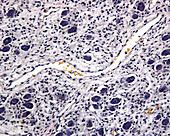

12627656 - Colon Adventitia, LM